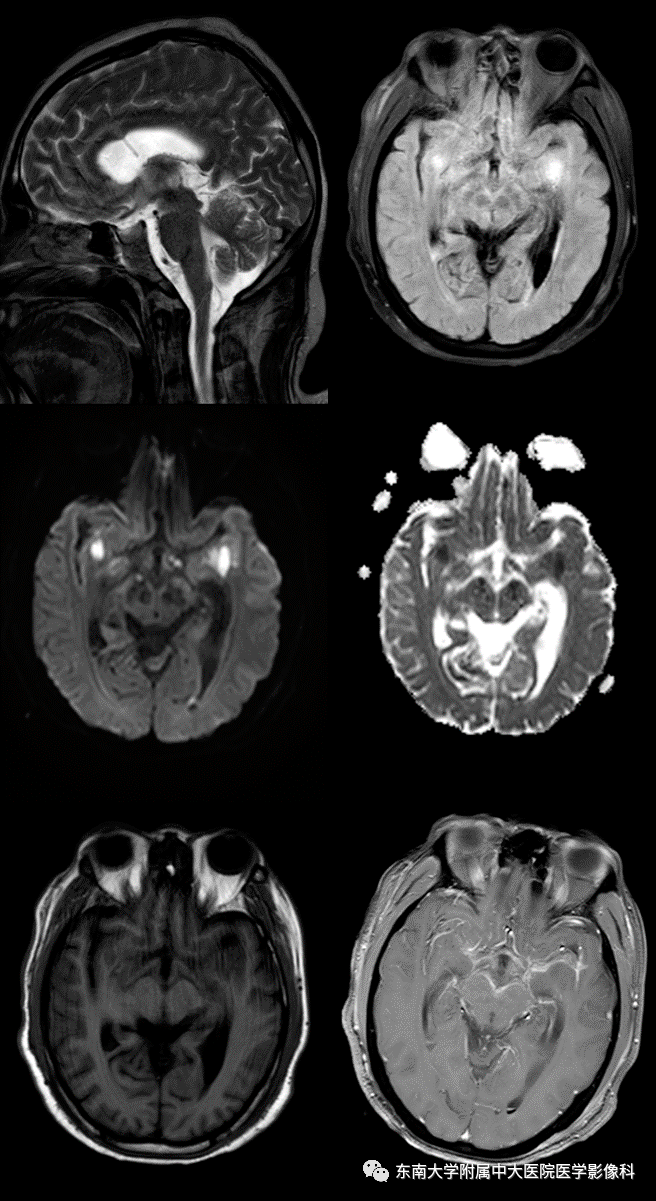

病史 男,44岁,因"头痛20余天,发热13天"入院 mr 平扫 增强

图片尺寸656x1201